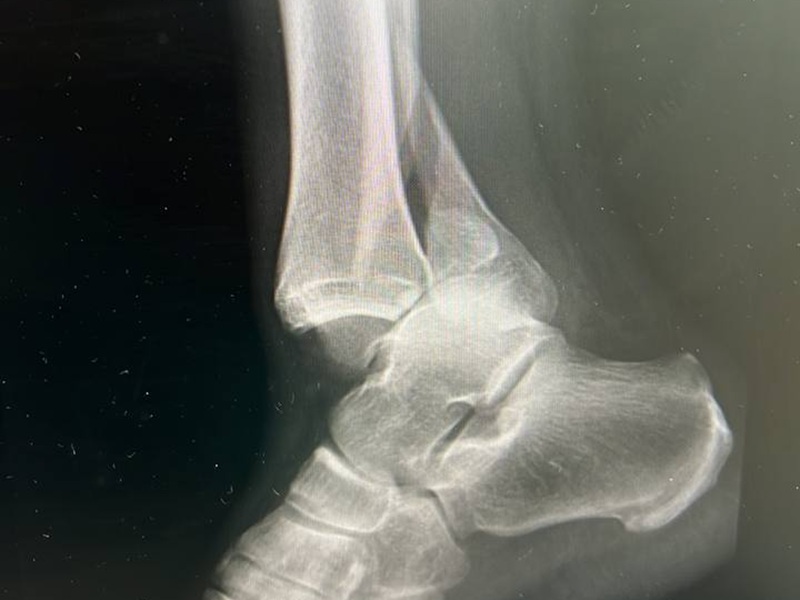

- зміщення, підвивих або вивих суглоба;

- переломи кісток, тріщини, наслідки травм;

- Знімок суглоба. Рентген-апарат фіксує зображення у цифровому або плівковому форматі. Лікар може зробити рентген суглобів в одній або кількох проекціях (фронтальна, бокова, коса) — залежно від поставленого діагностичного завдання.

Найчастіше обстежують колінні, кульшові, плечові, ліктьові, гомілковостопні суглоби, а також суглоби кисті. Це пов’язано з частотою травм і навантаженням на ці зони. Також проводять рентген для контролю стану після протезування або при артрозі.